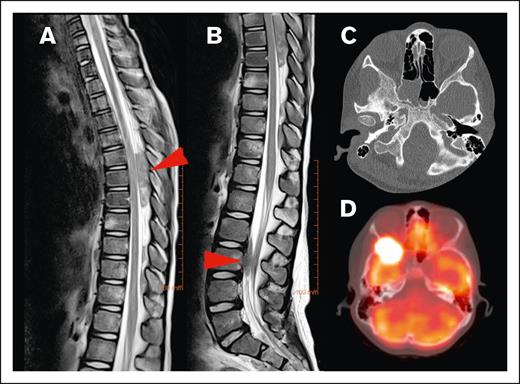

None of the lesions involved the intra-axial CNS space. All lesions extended into the extra-axial CNS space from surrounding tissue. At the time of diagnosis, the majority of patients (82.2%) had a single lesion involving the CNS, whereas 4.4% had up to 3 discrete lesions in the CNS. The lesions extended into the thoracic spine (45.5%), sacrum (23.6%), lumbar spine (21.8%), cervical spine (5.5%), and skull (3.6%; Figure 2). In our cohort, 45% of lesions originated from adjacent bone and 40% from adjacent soft tissue. We were unable to determine the tissue of origin for 15% of lesions (Figure 3).

Locations of HL CNS involvement. (A) Tumor in the dorsal part of the thoracic spinal canal and (B) ventral part of the lumbar spine (T2-weighted MRI sequences of the same patient, red arrow indicating tumor location), (C) tumor originating from the skull (bone window with subtle osteolysis, and (D) PET-fusion demonstrating the same lesion as in panel C extending into orbit and middle cranial fossa.